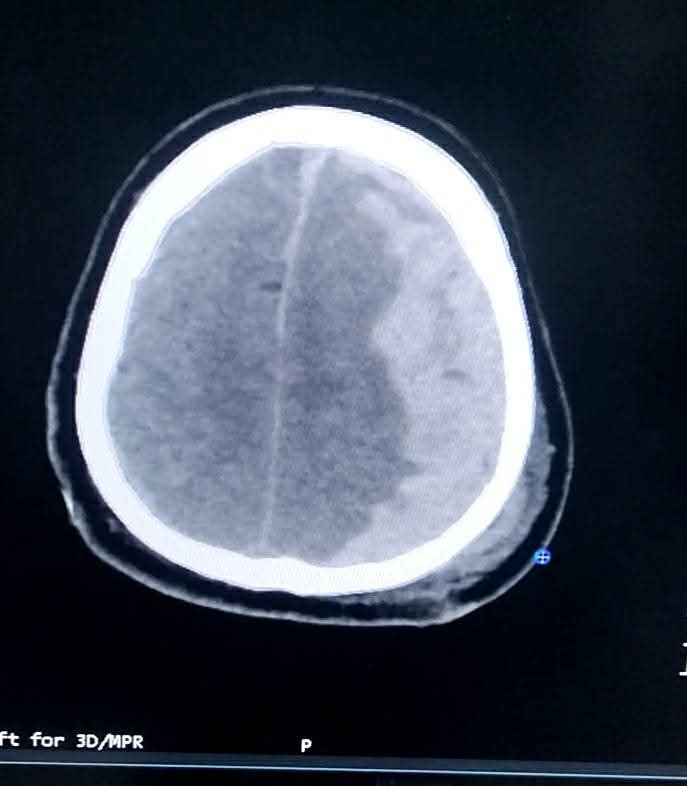

Під час детального огляду лікарі діагностували вкрай небезпечний клінічний стан — тріаду Кушинга:

Брадикардія (критичне сповільнення серцебиття);

Високий артеріальний тиск;

Патологічне дихання.

Це поєднання симптомів свідчить про те, що внутрішньочерепний тиск сягнув критичної позначки, фактично «тиснучи» на мозок зсередини.